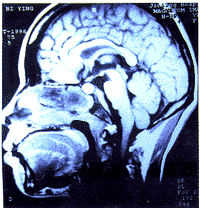

2.1 颅底骨受累的部位:全组128例患者中,97例有颅底骨受累(经反复阅片),占75.8%(97/128), 其发生部位以斜坡最为常见,占81.4%(79/97), 其次为蝶骨46.4%(45/97)、岩骨44.3%(43/97),单一部位仅占24.7%(24/97)。破坏斜坡脑面出现硬脑膜强化增厚者21例占16.4%(21/128),其中头痛者19例占90.5%(19/21),颅神经阳性者17例占81.0%(17/21), 6例放射治疗后0~14个月再行MRI检查的患者, 强化增厚的硬脑膜全部恢复正常或明显变薄(见图1)。

a 放射治疗前斜坡脑面硬脑膜明显变厚(黑箭头所指)

b 放射治疗后全部恢复正常

图1 放射治疗前、后的颅MRI片